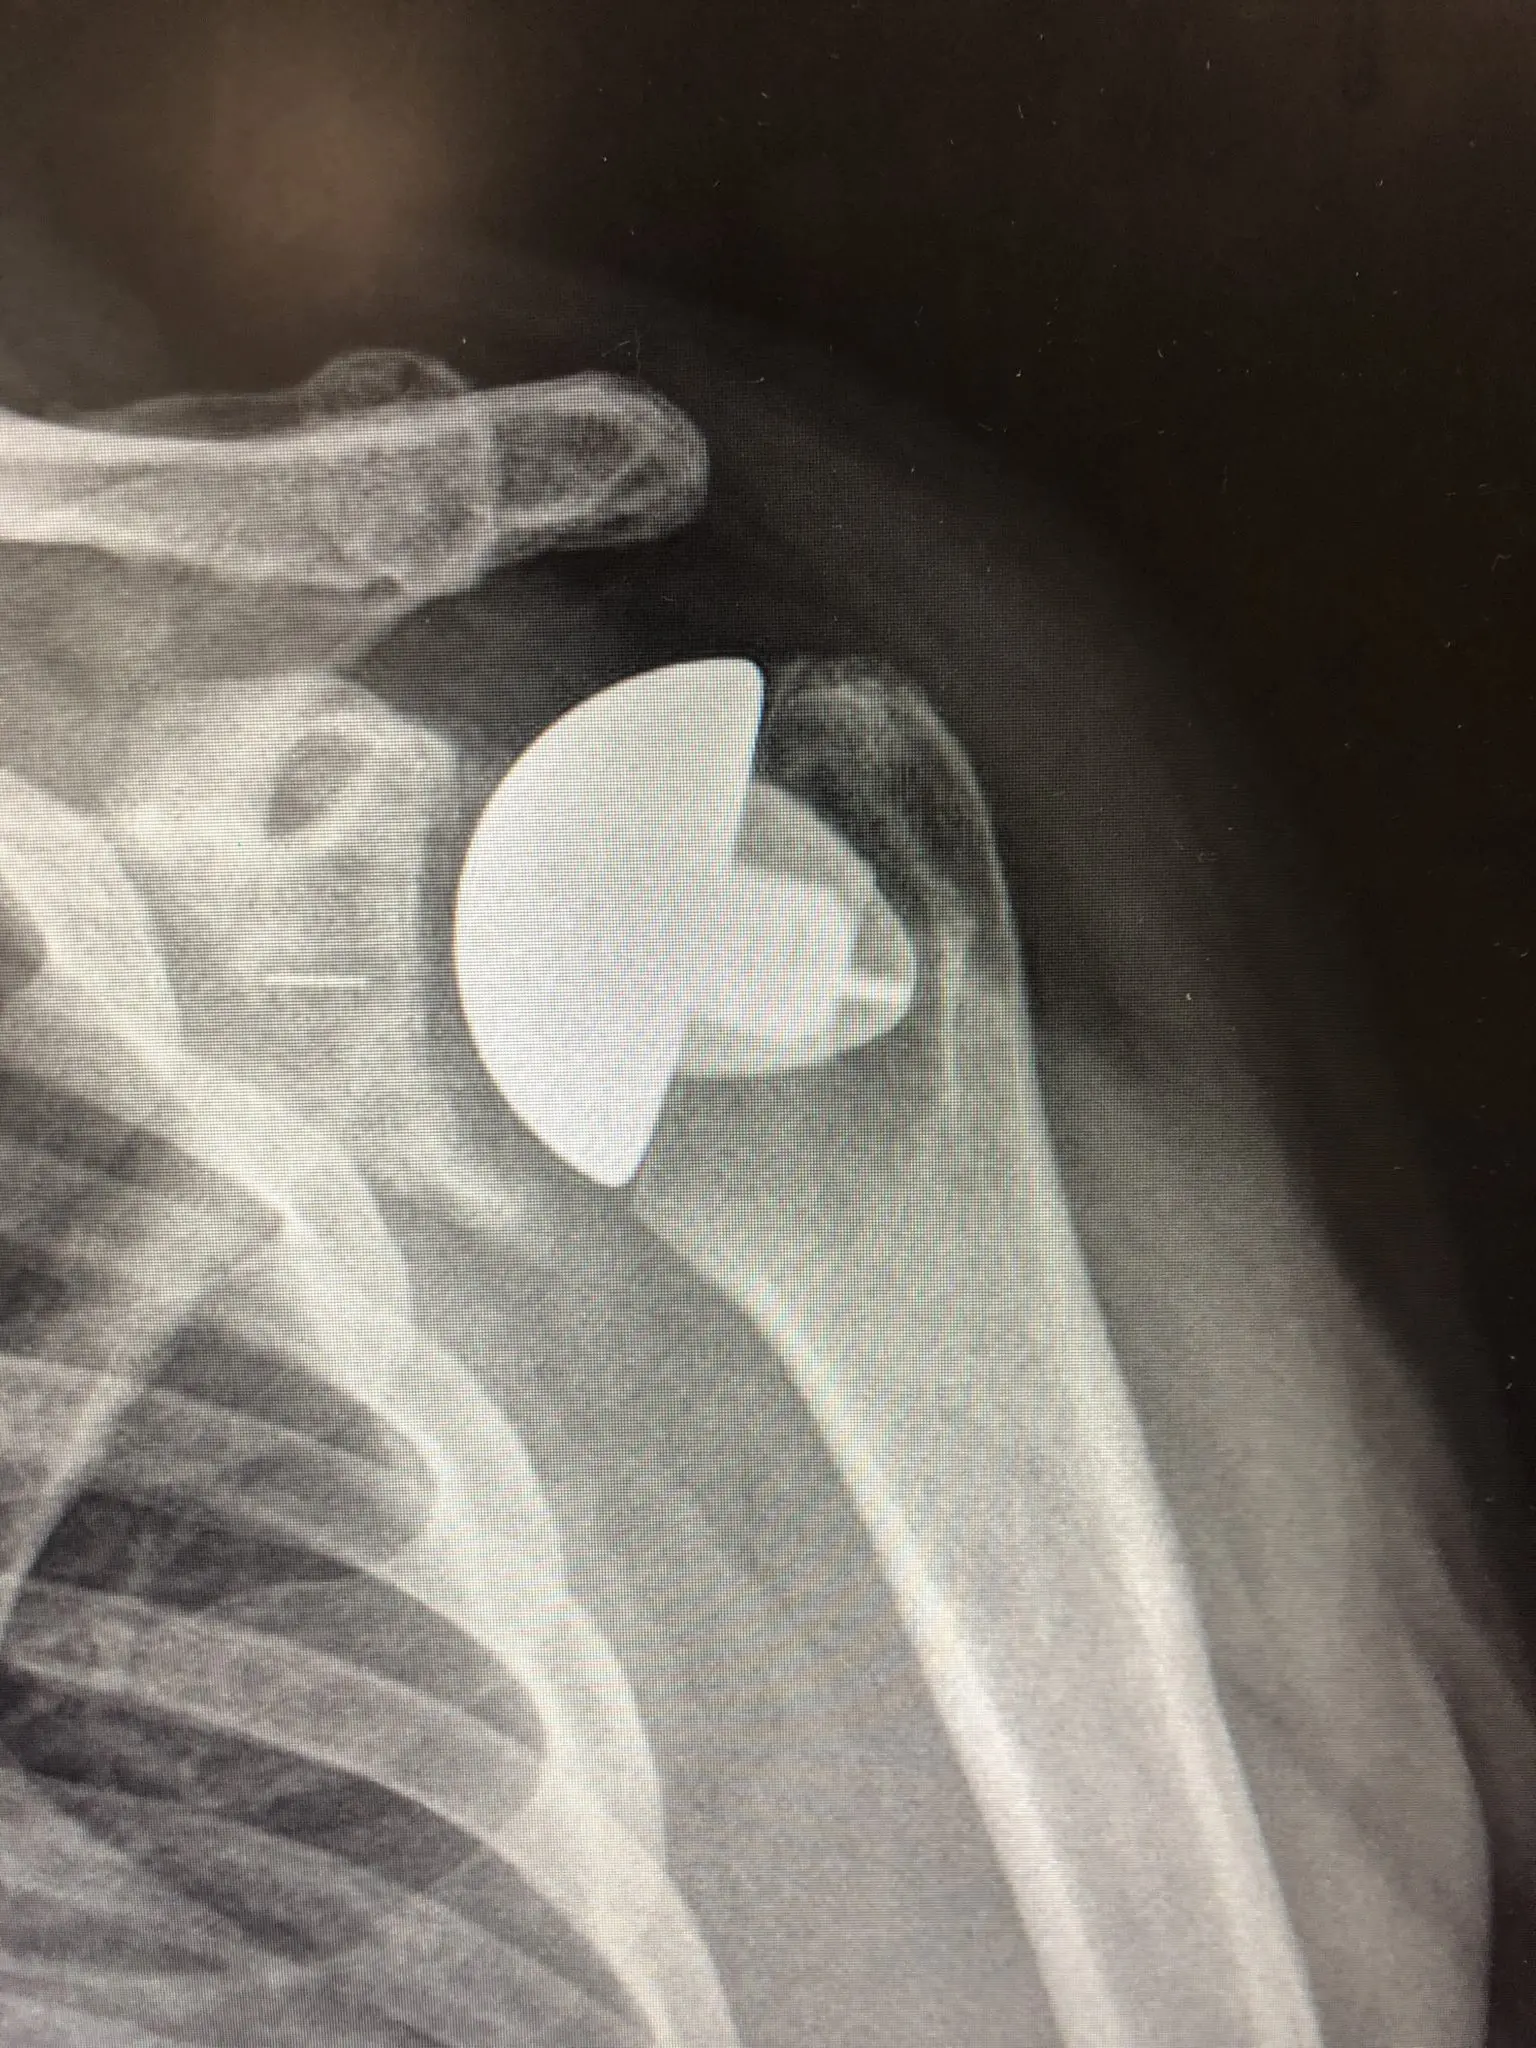

RTG - shoulder replacement

If degenerative changes are more advanced, recovery and return to activity is secured by shoulder replacement, namely the worn joint surface. The joint replacement surgery takes about two hours. After the procedure, the arm is fixed in an orthosis for 4-6 weeks, so that the cut tendons have time to heal. During this period, shoulder exercises are implemented under the control of a physiotherapist. Return to daily activities and driving takes about 6 weeks, to sports activities - 3-6 months. Total recovery lasts up to 12 months.

Over the past 20 years, shoulder arthroplasty has become the standard in the treatment of shoulder degenerative changes worldwide. Currently, there are 3D (three-dimensional) reconstruction options, allowing personalization of the endoprosthesis and its precise adaptation to patient's body, thus reducing the risk of early loosening and other complications.